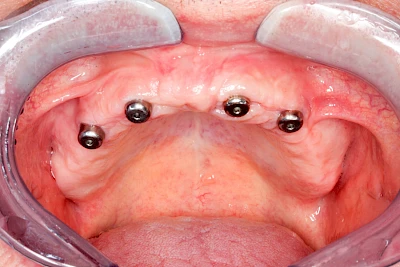

Implantate: Prothesen

Bei herausnehmbaren Prothesen werden Implantate eingesetzt, um den Halt und den Tragekomfort der Prothesen zu verbessern. Dazu kommen verschiedene Verbindungselemente zum Einsatz:

- Teleskope

- Kugelköpfe

- Tellerförmige Lokatoren

- Stege

- Magnete (selten)

Neben rein implantat-getragenen zahnärztlichen Versorgungen werden bei herausnehmbaren Prothesen Implantate auch in Sinne einer "strategischen Pfeilervermehrung" ergänzend zu eigenen Zähnen zur Verankerung eines Zahnersatzes genutzt.

Varianten zur Verankerung von abnehmbarem Zahnersatz auf Implantaten